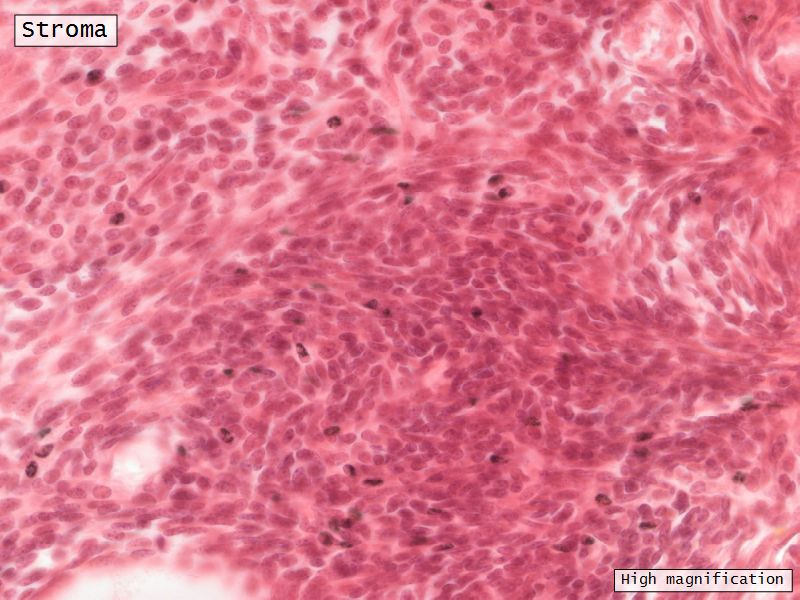

Stroma

- Highly cellular loose CT

- Fibroblasts

- Elastic & collagen fibres

- Form layers around follicles